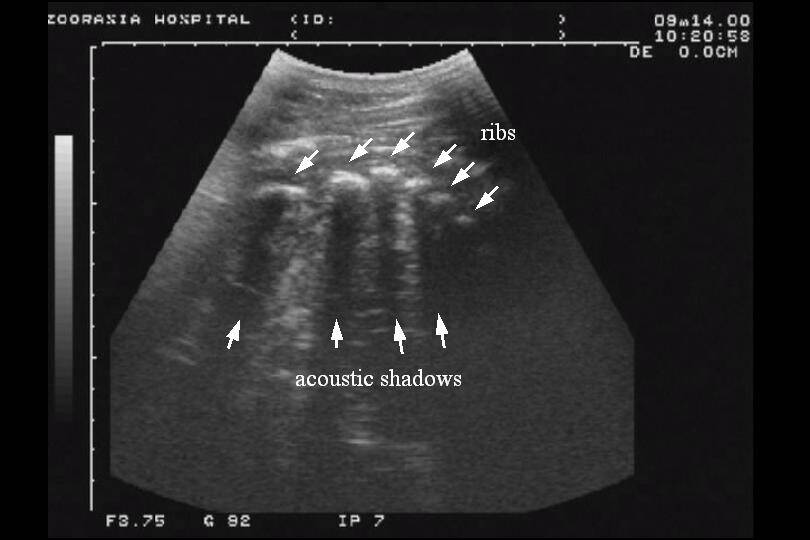

当時はまだアフリカの熱帯雨林ゾーンはできておらず、今、モウコノロバを飼育している場所で飼育していました。エコー検査で妊娠が確認された時の喜び。モニター越しに出産が確認された時の感動。順風満帆のように進んでいました。この先に待ち受けていた衝撃を見るまでは・・・

↓ これがエコーの画像です('ω')ノ